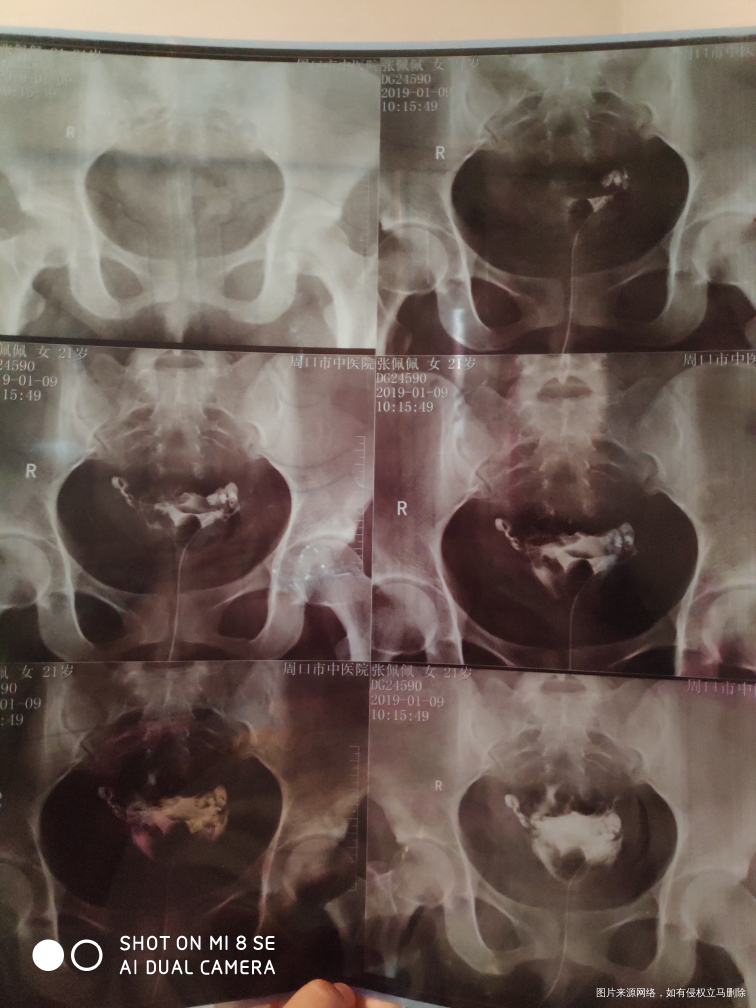

做的造影 看下有没有什么问题

输卵管造影显示双侧输卵管是通畅的,可以2个月后备孕,排卵期在下次月经来的前14天左右,可以排卵期增加同房次数,提高怀孕机率。也可以月经期第10天开始做彩超监测卵泡,等卵泡长18mm以上为成熟卵泡,那时可以安排同房,隔天一次,看卵泡能否排出,不能排出可以肌注人绒毛膜促性腺激素10000u促进卵泡排出,可以排卵后10天化验血hcg,或排卵后14天早孕试纸测一下怀孕。祝好孕,孕前3个月至孕3个月口服叶酸预防胎儿脑神经畸形!如果我的回答对你有帮助,请采纳!谢谢